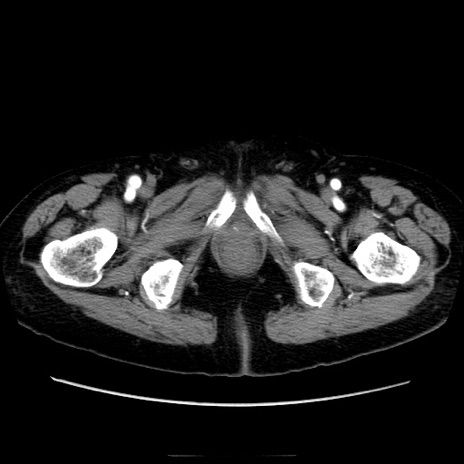

症例21(横断像)

【症例】70歳代男性

【主訴】腹痛

【現病歴】肝硬変・肝細胞癌にてかかりつけの方。約9時間前に食後より腹痛出現。症状が徐々に増悪し、嘔吐出現したため来院。

【既往歴】肝硬変、肝細胞癌(RFA、TACE後)

【身体所見】意識清明、表情苦悶様、BT 36℃、BP 129/78mmHg、P 88bpm、SpO2 97%(RA)、右上腹部から心窩部にかけて圧痛あり、反跳痛なし、筋性防御あり。

【データ】WBC 5800、CRP 0.16